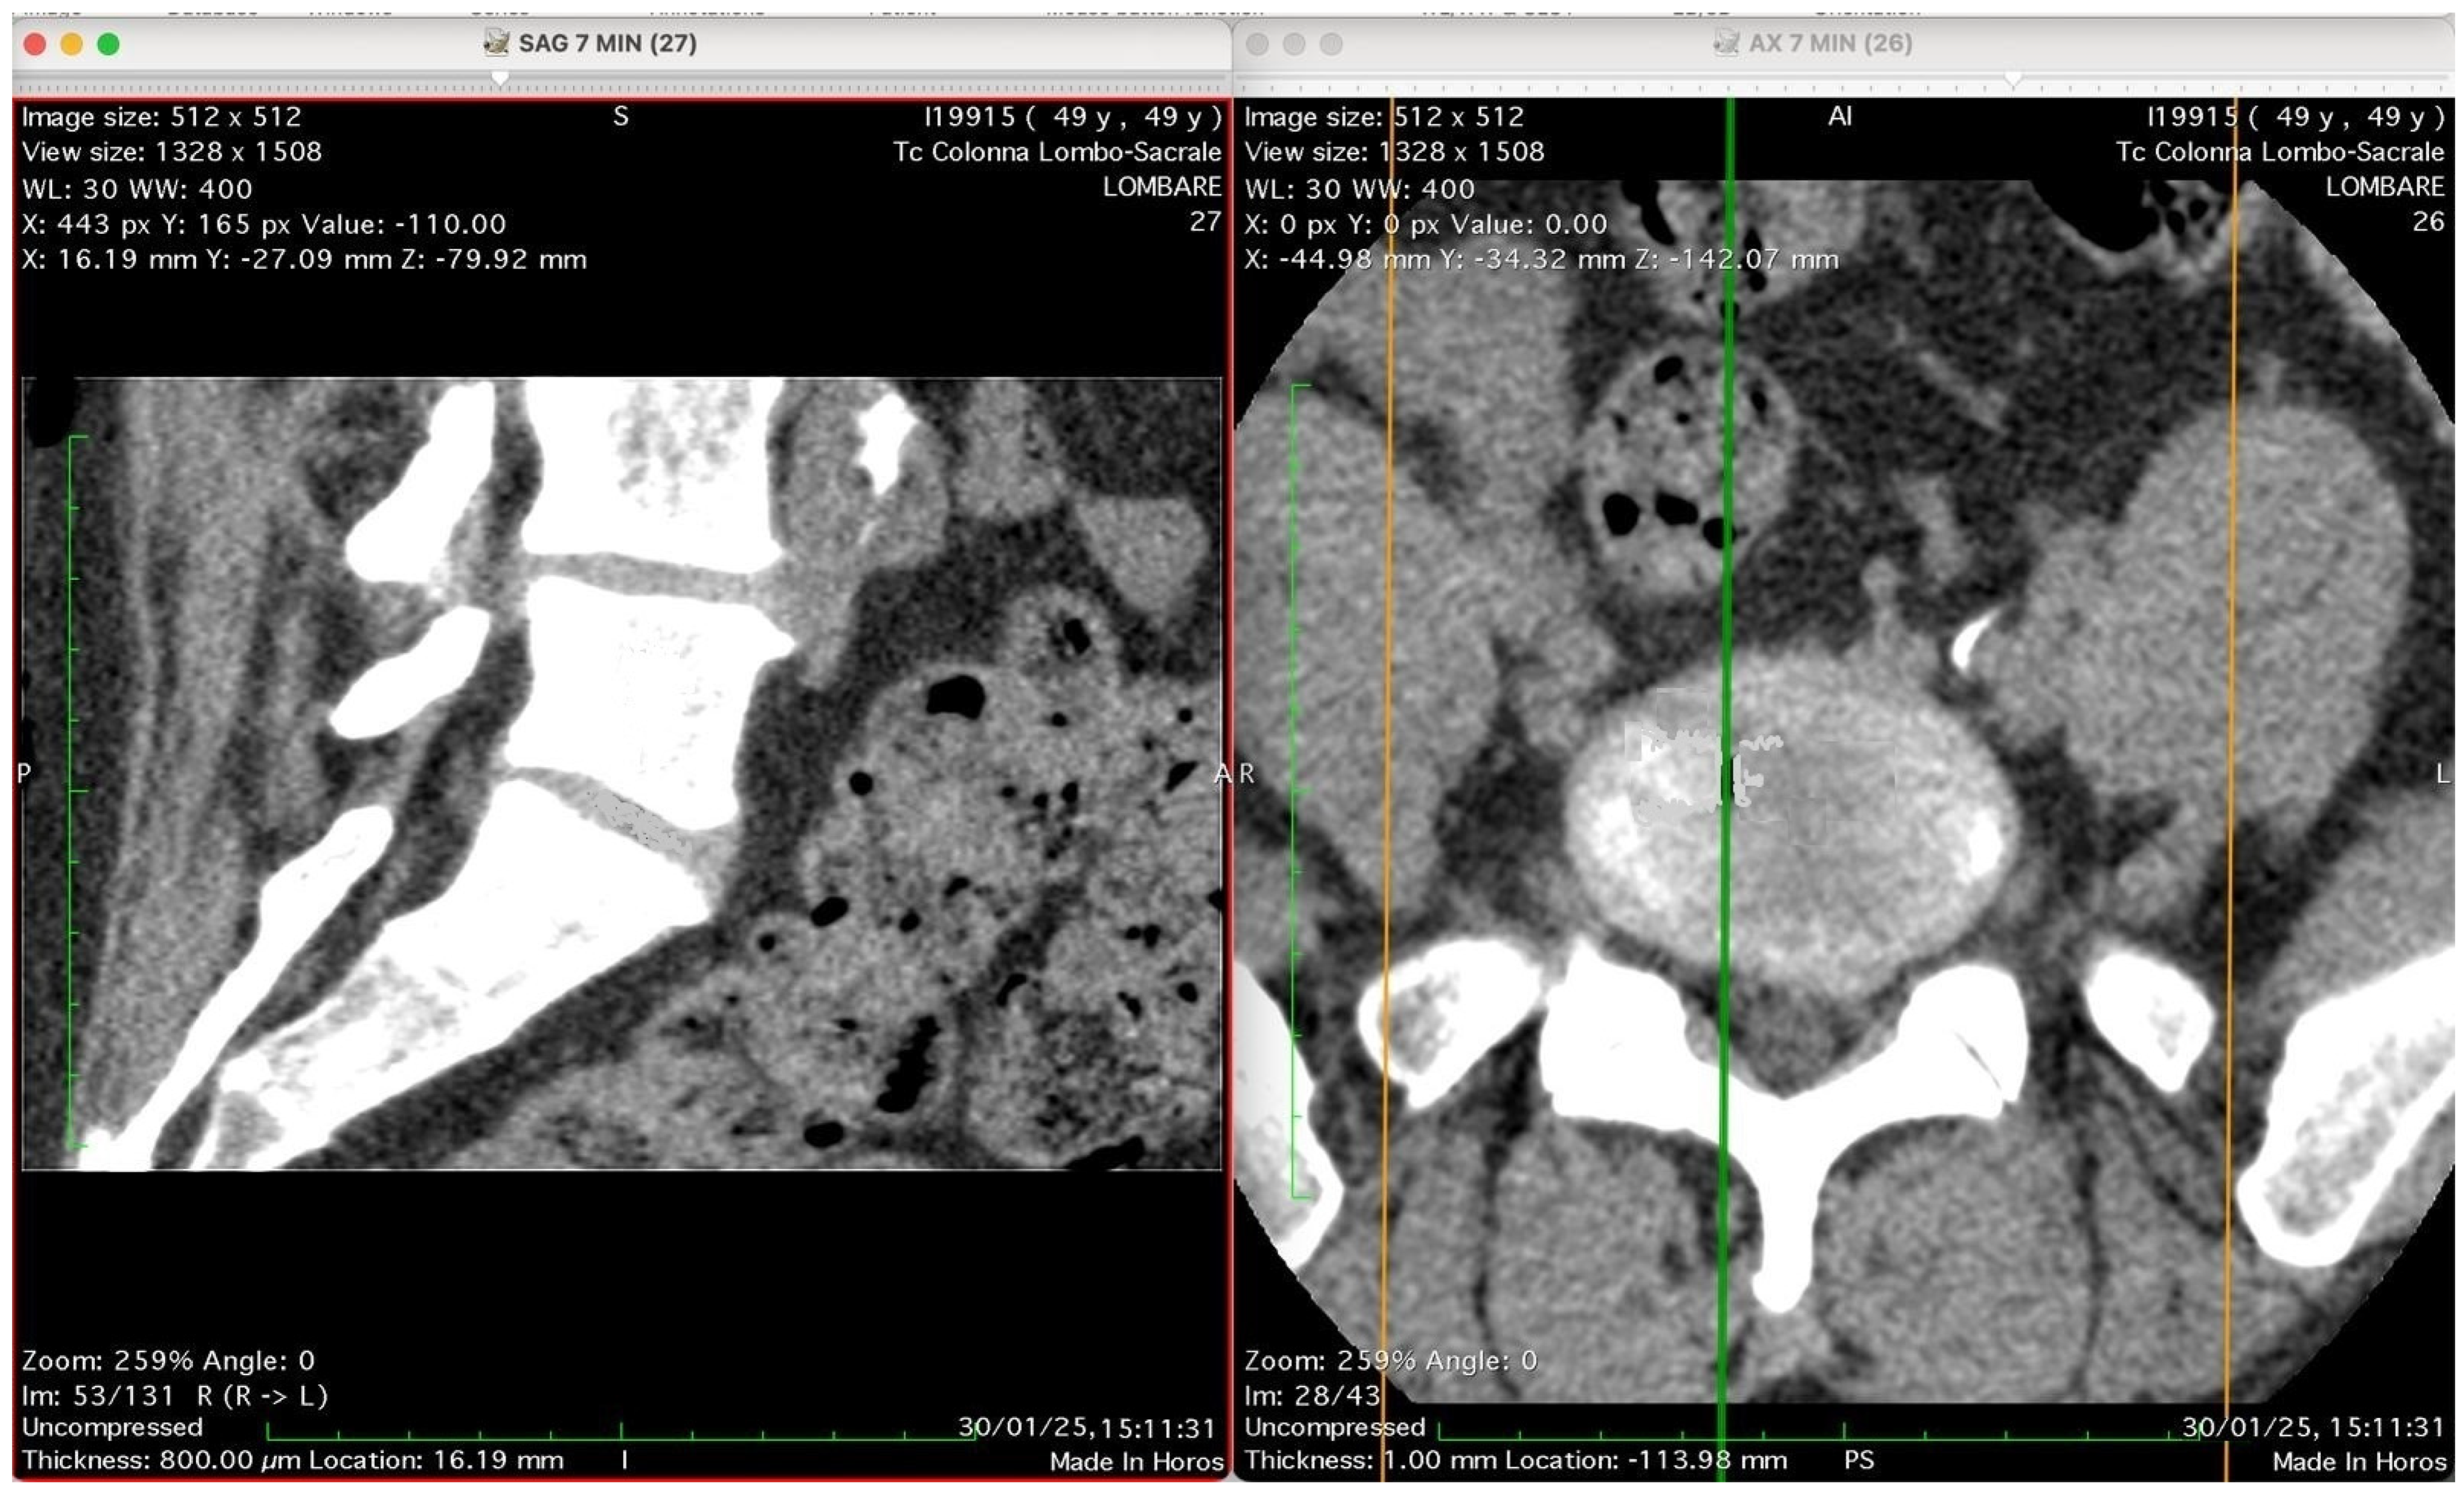

Figure 2, Figure 3, Figure 4 and Figure 5 show four computed tomography (CT) scans, along a time-course analysis, of the lumbosacral spine, visualized in sagittal (left) and axial (right) planes, from an exemplificative male patient (49 years) with L5-S1 herniated disc, undergoing an experimental setting of oxygen–ozone therapy via the intramuscular approach (Revolution™ CT, GE-Healthcare, Chicago, IL, USA). The very low-density ozone gas (hypodense, dark black within cred circles), spreads over the intervertebral disc within the time course of less than 10–20 min, assessing that ozone in the oxygen medium really reaches the morpho-functional area where the herniated disc is present in short times. A possible explanation is provided in the next paragraph.

Figure 2 shows two computed tomography (CT) images of the lumbar spine from a lumbosacral CT scan at time 0 (“Tc Colonna Lombo-Sacrale”), displayed in two standard planes. The left panel (SAG 7 MIN), shows a sagittal reconstruction through the lumbar region. The vertebral bodies, intervertebral discs, and spinal canal are seen in longitudinal profile. Gas-like hypodense areas (black regions) are still not visible in the intervertebral disc spaces, as this is the time 0, when present these correspond to intradiscal gas, consistent with vacuum phenomenon or possible gas introduced by percutaneous-intramuscular injection. The soft tissues and paravertebral structures are also visible. Right panel (AX 7 MIN) shows an axial slice at a corresponding lumbar level. The spinal canal is centrally located, surrounded by vertebral bone. The alignment of the green and orange cross-reference lines indicates the plane correspondence between sagittal and axial images. Technical details (as annotated in the image): Matrix size: 512 × 512 Window/Level (WL/W): 30/400 (bone-soft tissue contrast) Slice thickness: 0.8 mm (reconstructed to ~16 mm view) Scan date: 30 January 2025 Interpretation summary: The image pair represents a CT lumbosacral segment showing intradiscal and paravertebral gas, likely associated with degenerative disc disease or following paravertebral oxygen–ozone therapy. The correspondence between sagittal and axial planes allows correlation of gas location relative to the disc and vertebral bodies.